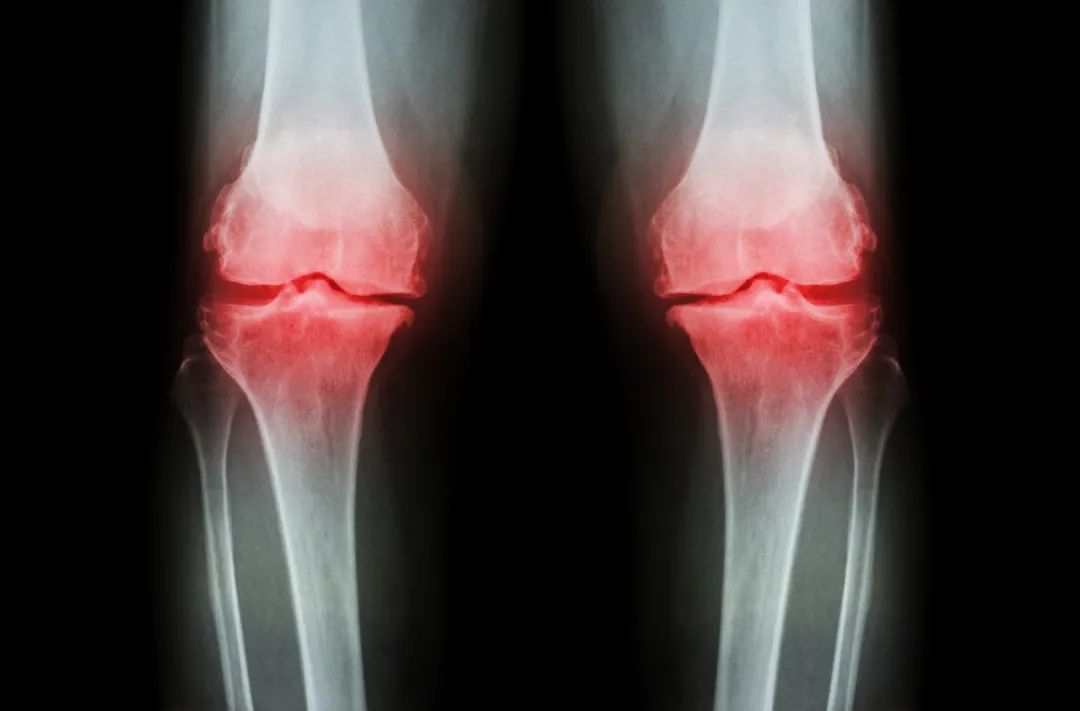

PRP治疗膝关节炎

有的研究将PRP用于膝关节镜术中作为治疗KOA的辅助疗法。Duif等在一项随机对照双盲试验中,将58例拟行膝关节镜的KOA患者随机分为两组,24例患者术中辅以PRP关节腔注射,34例患者仅行关节镜手术,评估患者疼痛、功能及生活质量变化。结果示PRP组患者6个月内疼痛明显缓解。也有研究将关节镜微骨折术与PRP相结合用以治疗KOA。Manco等在一项前瞻性试验中将患者分为两组,A组30例患者采用微骨折手术,B组14例患者术中联合PRP治疗。结果显示两组患者VAS评分降低,而B组的评分值在短期内更好。作者认为自体PRP结合微骨折术有更好地短期临床疗效。